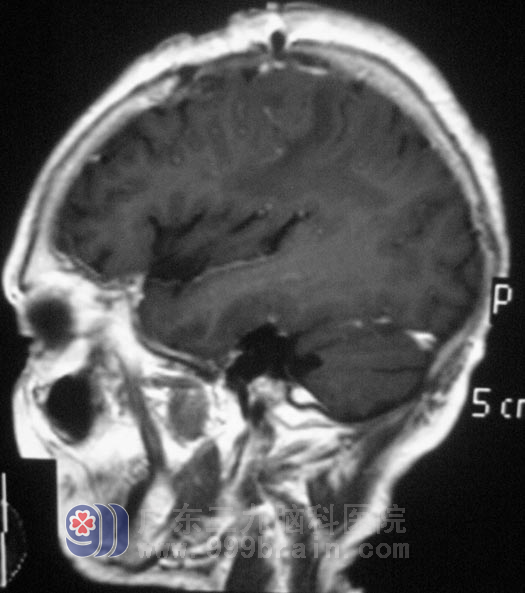

好心的邻居提醒她:“去做个检查看看,有病早治疗,没病就权当为自己做个体检”。在当地医院行MR检查,结果提示:左侧额顶叶占位,医生考虑脑膜瘤可能,建议手术治疗。http://www.999brain.com/

家里人选择了广东三九脑科医院,综合神经外科 鲁明主任也考虑脑膜瘤可能性大。

8月18日,由鲁明主任主刀,在全麻下行左侧额顶部占位切除术,术中见灰红色的肿瘤组织,肿瘤质软,前方与中央沟引流静脉粘连紧密,其余方向边界清,沿血管壁、肿瘤与脑组织分界处仔细分离肿瘤,肿瘤达辛普森I级切除。术后经过治疗,兰姨自诉右侧手掌部、足背部痛温觉较术前好转,不再有蚂蚁爬行的感觉。经病理证实为:(左额顶部)皮细胞型脑膜瘤,WHO I级。